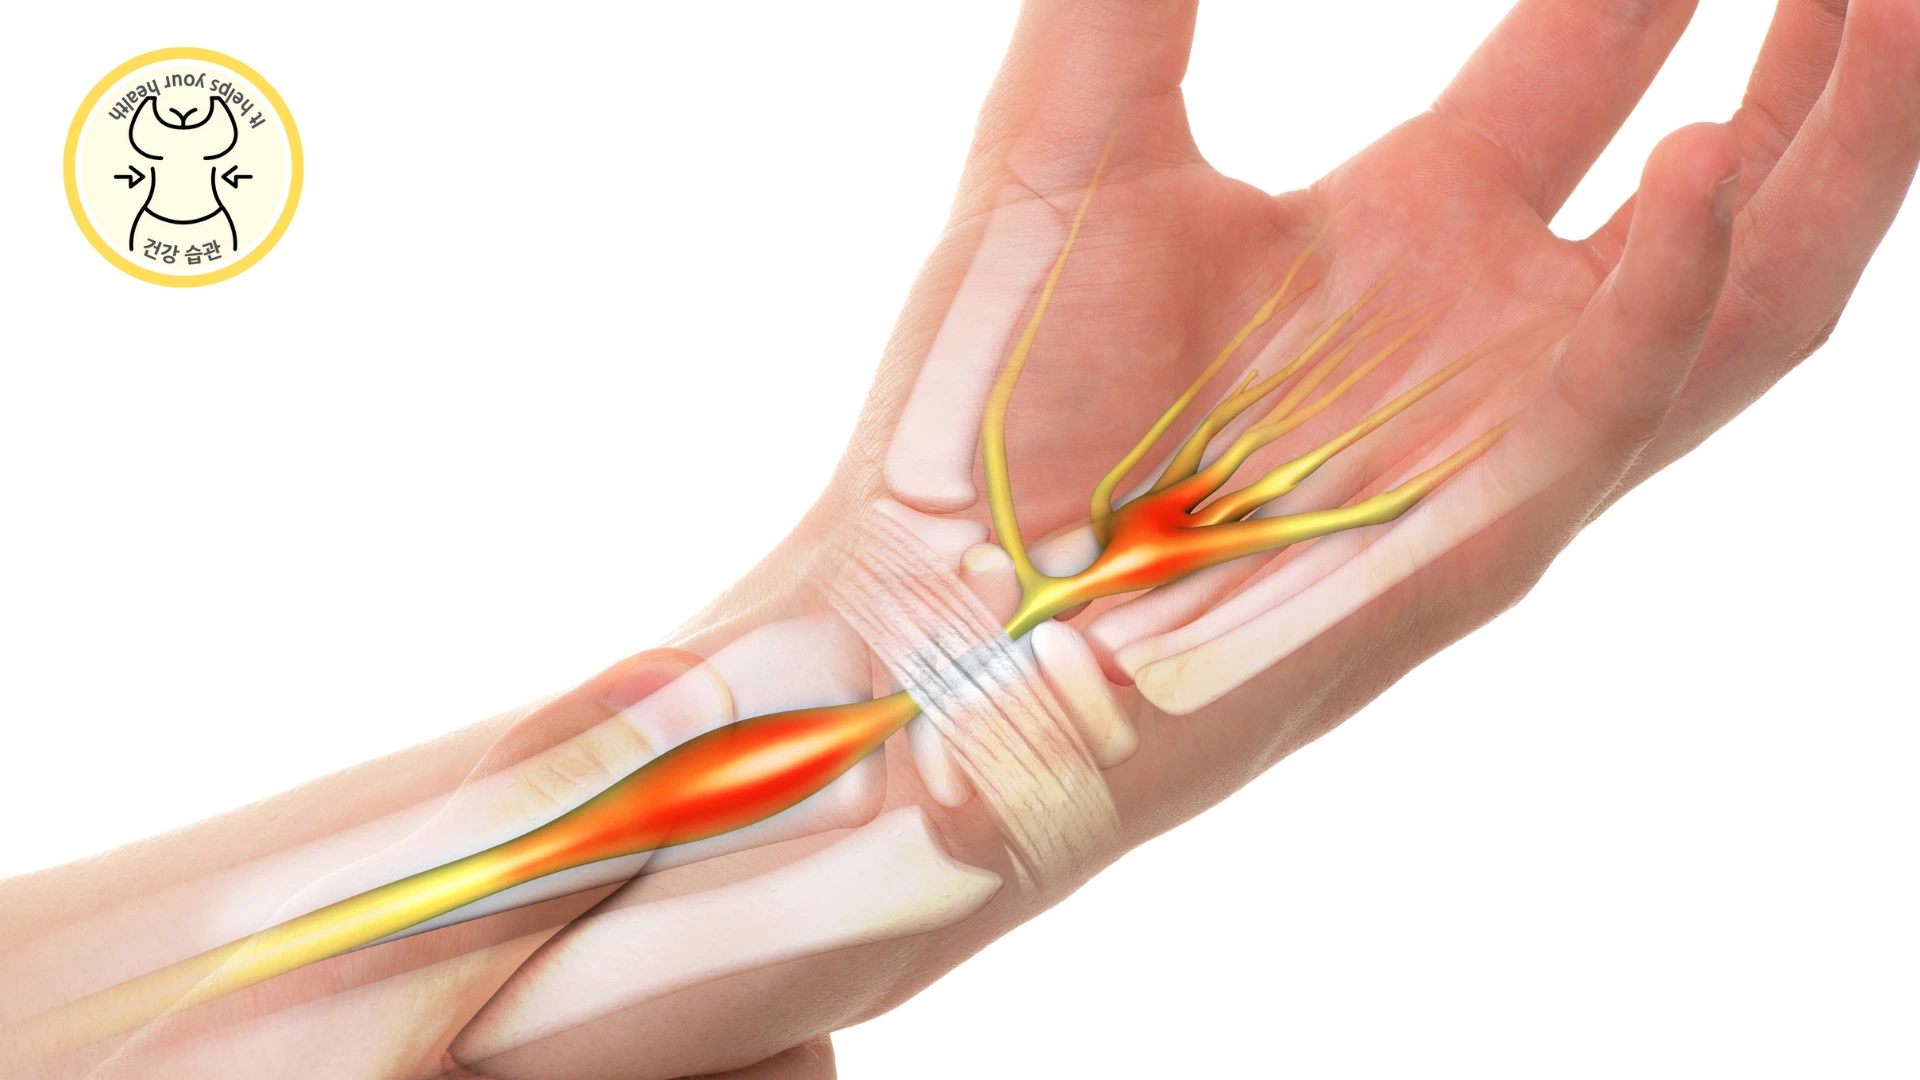

수근관증후군

손의 수근관을 관통하는 건막의 염증과 섬유화로 손목에 있는 정중 신경에 부종이 생기고 압박을 주게 되어 손데 통증과 감각마비가 나타나는 증상입니다. 대부분 컴퓨터나 손목을 많이 쓰는 사람에게 흔한 직업병으로 전체 인구의 약 3%에게 발병이 되며 30~60대 여성에게 많이 나타납니다. 손이 저리기 때문에 혈액순환이 안되는것 같아 병원을 방문하면 이 진단을 받는 경우가 많습니다.

- 수근관 증후군의 증상

- 통증, 감각마비, 저림

- 손에 힘이 빠짐, 주먹이 쥐어지지 않음

- 손목 부종

- 화끈거림

- 엄지 두 덩이의 위축(살이 빠짐)

- 엄지, 검지, 중지 약지의 감각 상실

가슴 앞에서 손등을 꺾어 마주했을 때 저림 감이 심해지면 이 질병을 의심해 볼 수 있습니다.